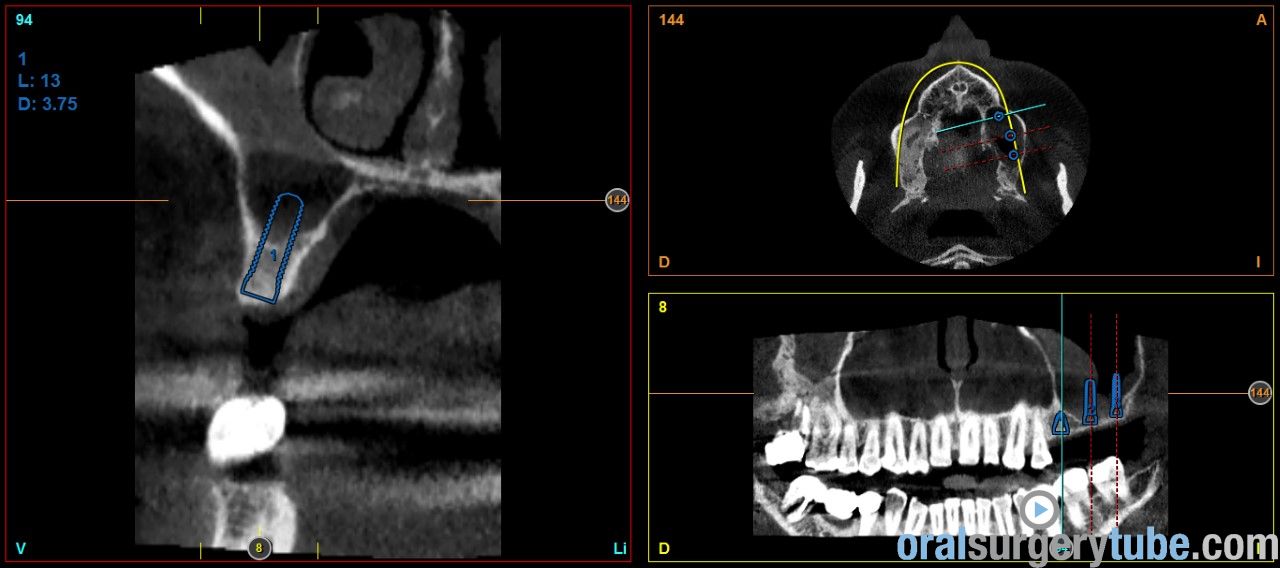

Engrosamiento mucoso

Estimados compañeros, me gustaria saber como abordaríais el seno izquierdo el cual como veis presenta engrosamiento mucoso. Haríais tratamiento previo? Gracias de antemano

Que opináis de dar un corticoide vía oral? Como la dexametasona?. Por cierto repetí el tac después de hacer la elevación derecha y de dar antibiótico y la verdad que el engrosamiento del sebo izquierdo a cambiado más bien poco por no decir que incluso se ha engrosado un poco más, pero eso sí, el paciente no refiere haber tenido en toda su vida síntomas de sinusitis ni alergia, imagino que la causa es la desviación que se ve del tabique hacia la izquierda y la concha bullosa del cornete medio, de verdad no se q hacer, si abordar el seno así ( ya que el paciente no tiene síntomas ) o derivarlo a un otorrino.Tampoco me parece exagerado el engrosamiento, qué opináis?

Hola a todos. Al hilo de este post que he visto, os presento un caso que me ha llegado hace poco a la consulta. Os envío imagenes. Se aprecia engrosamiento de la membrana del seno maxilar izdo. Pensaba darle Trigon Depot 10 días antes de la cirugía y luego valorar. Como lo veis? Muchas gracias.

Yo le pincharía corticoides al paciente; me encanta el trigon depot ( acetánido de triancinolona), intramuscular 15 días antes de la cirugía, luego a la semana, y repites el cbct. casi seguro que te encontrarás la mucosa normal. En caso de antecedente alérgicos del paciente, le asociaría un antihistamínico, me gusta la loratadina. Ya me dirás cómo te va. Recibe un abrazo, y disculpas por el retraso.